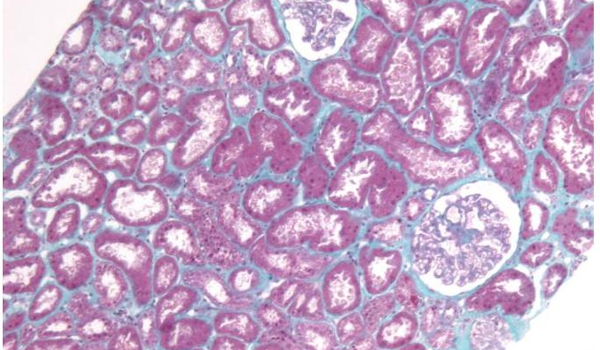

L’essai RENATO est un essai de phase 3, multicentrique, randomisé, contrôlé, en double aveugle, visant à évaluer l’efficacité de la pioglitazone pour promouvoir la récupération rénale dans la vascularite associée aux ANCA.